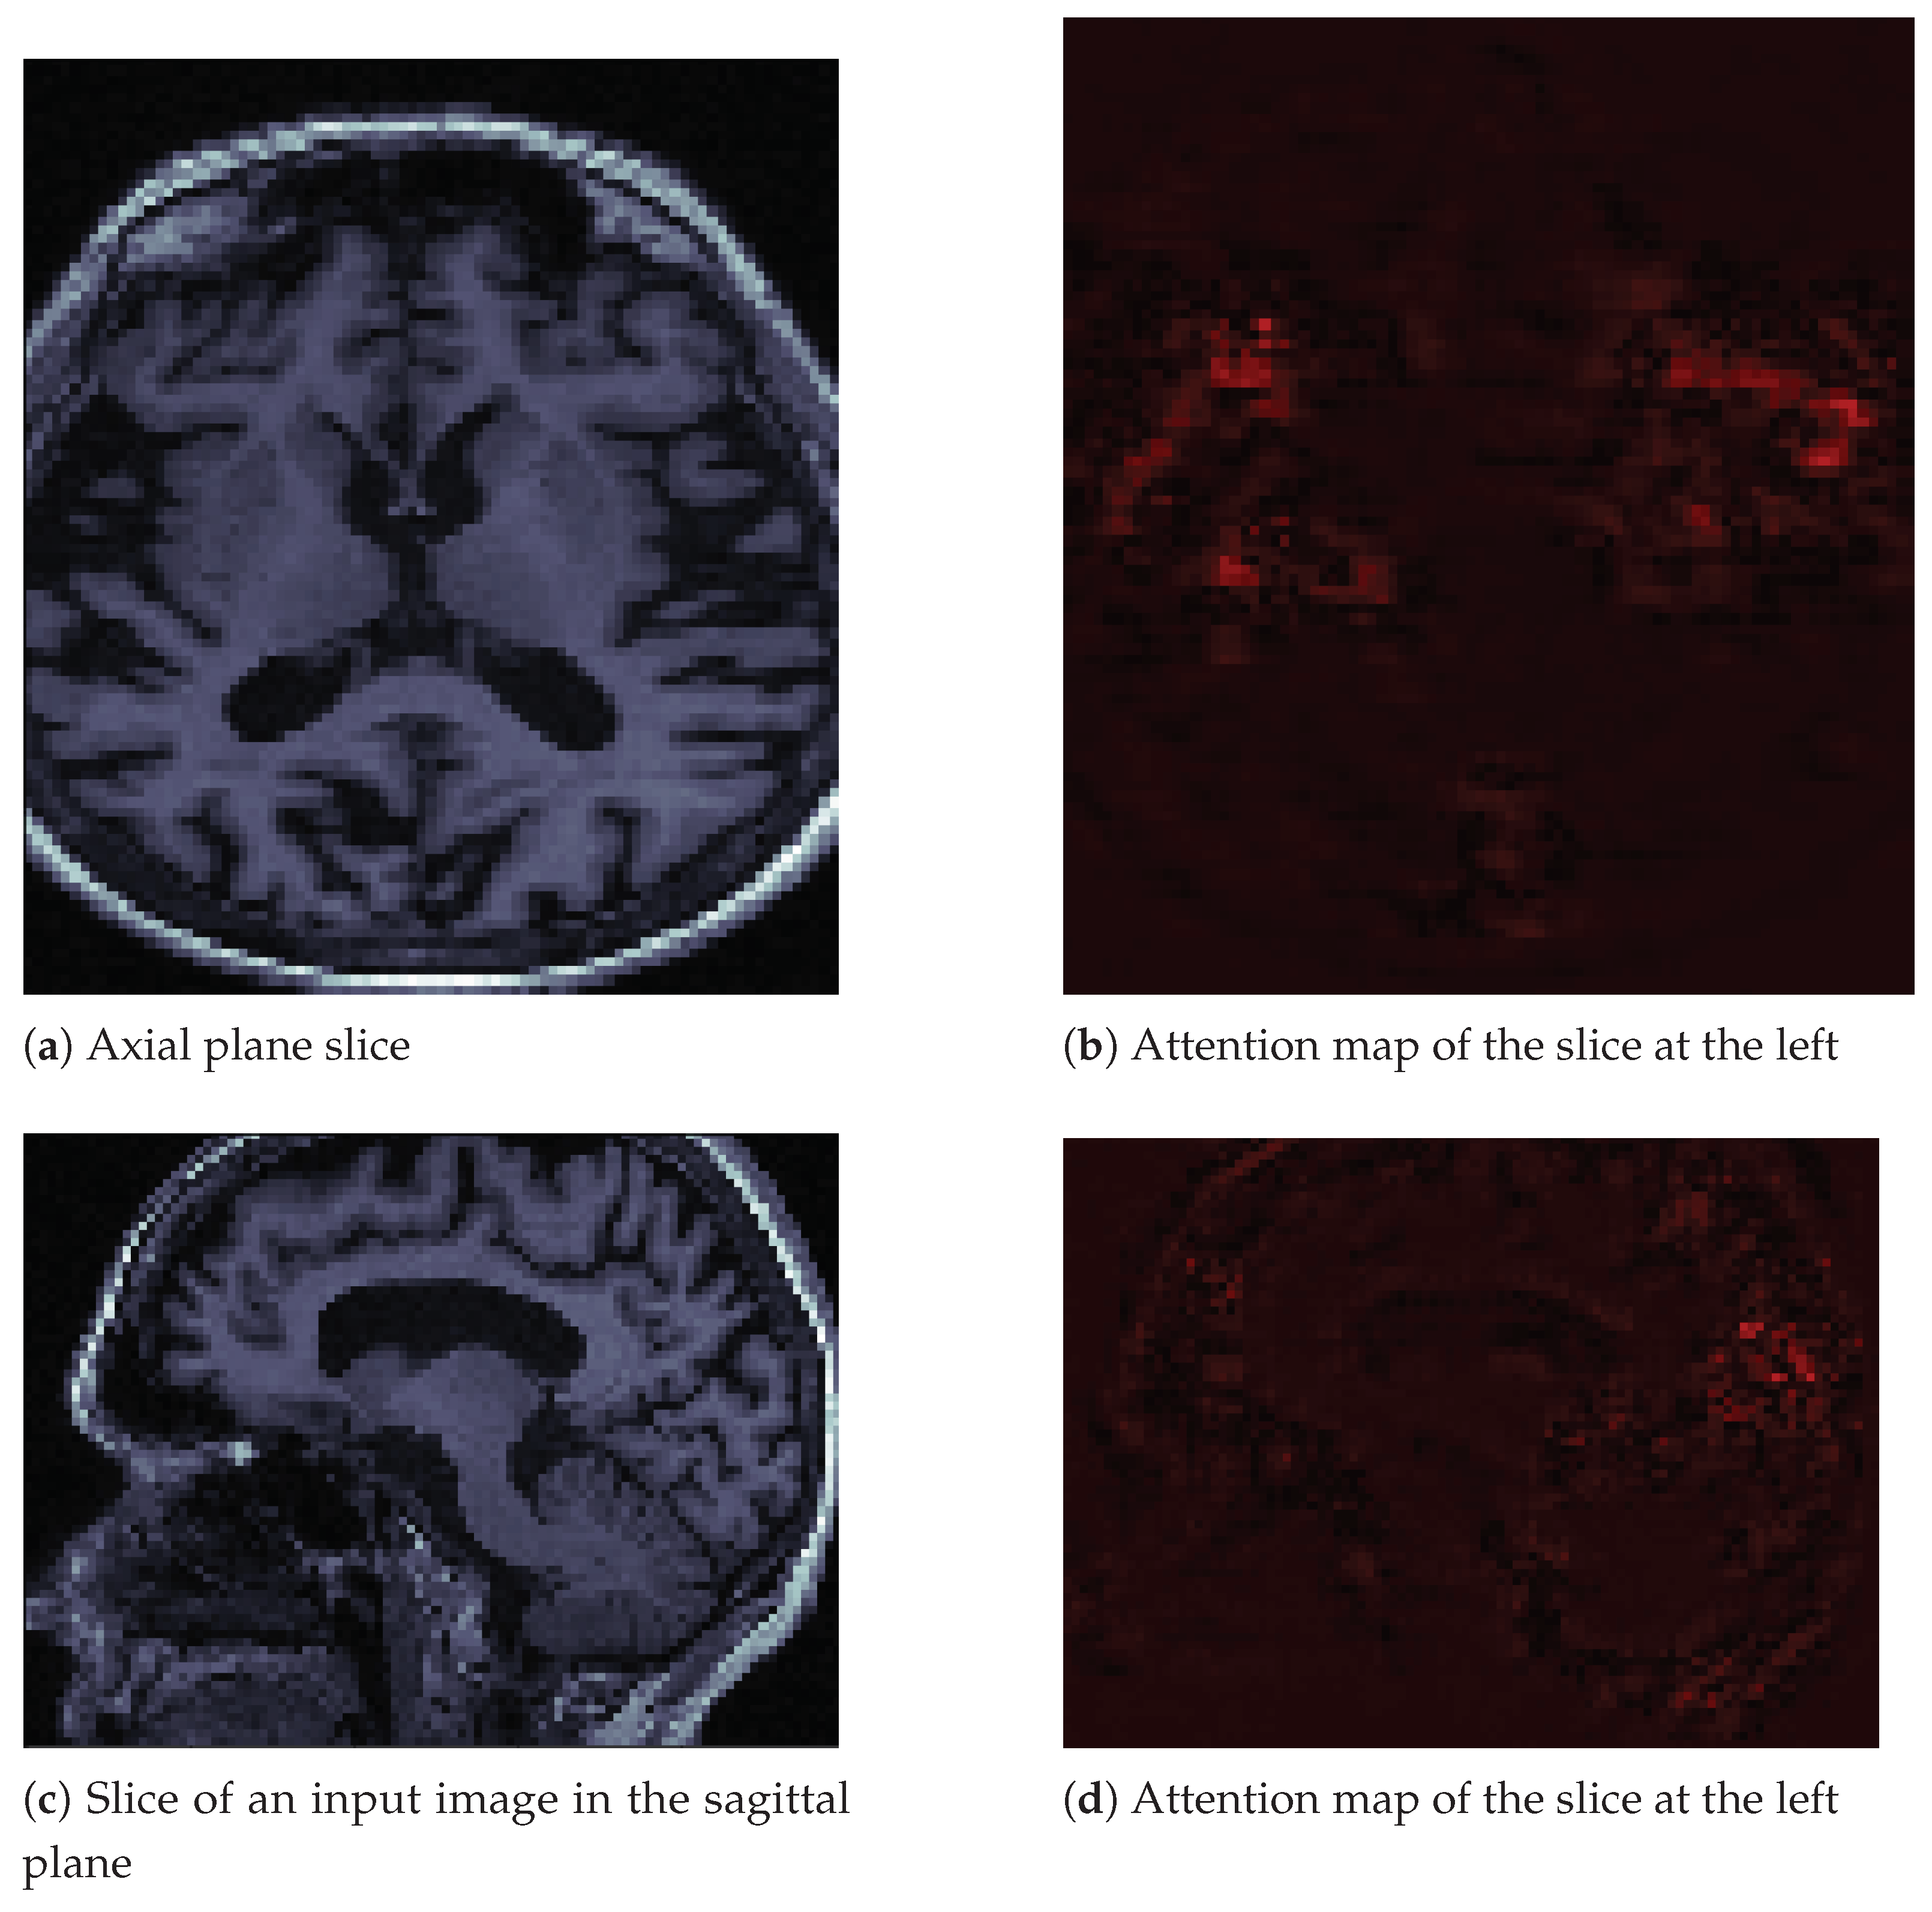

6.1. Attention Maps

Attention maps are visual tools that explain deep convolutional neural networks [33]. We used the M3d-Cam tool [34] with the Guided Gradient-weighted Class Activation Mapping (Grad-CAM) algorithm. We generated new images through M3d-CAM, and with these images, we could interpret what the neural network was emphasizing to make a decision. For example, in Figure 6a, we can see an image in the axial plane of a person with Alzheimer’s disease. We extracted only one slice of the cuboid. To its right, in Figure 6b, we can see that the neural network focuses its attention on brain atrophy. We extracted the same slice number from the attention map cuboid. In Figure 6c,d, we see the same patient and the same features in the sagittal plane. We also only extracted one slice of that plane.

Figure 6.

Input image slices and their attention maps from an MRI of a patient with AD.

In the images in Figure 6, we can see how brain atrophy areas appear more prominent. We noticed this behavior in other images for which we produced attention maps. The behavior of the network was as expected in terms of identifying the regions of importance. However, we also noticed that sometimes the neural network gave importance to bony areas of the skull or even to areas outside the skull. In other words, the attention maps seemed to have a potential function as debugging tools. Besides, they allowed us to propose solutions. We believe that we must improve the preprocessing of images by removing the skull using a mask, as the skull is a potential source of noise. This background noise could explain some of the classifier’s inaccurate results, as observed in the confusion matrices. The neural network may be learning uninformative features or patterns as a result of excess inputs. We could improve the results and reduce the inaccurate results by providing the CNN with only brain images, thus removing potential artifacts associated with the skull.